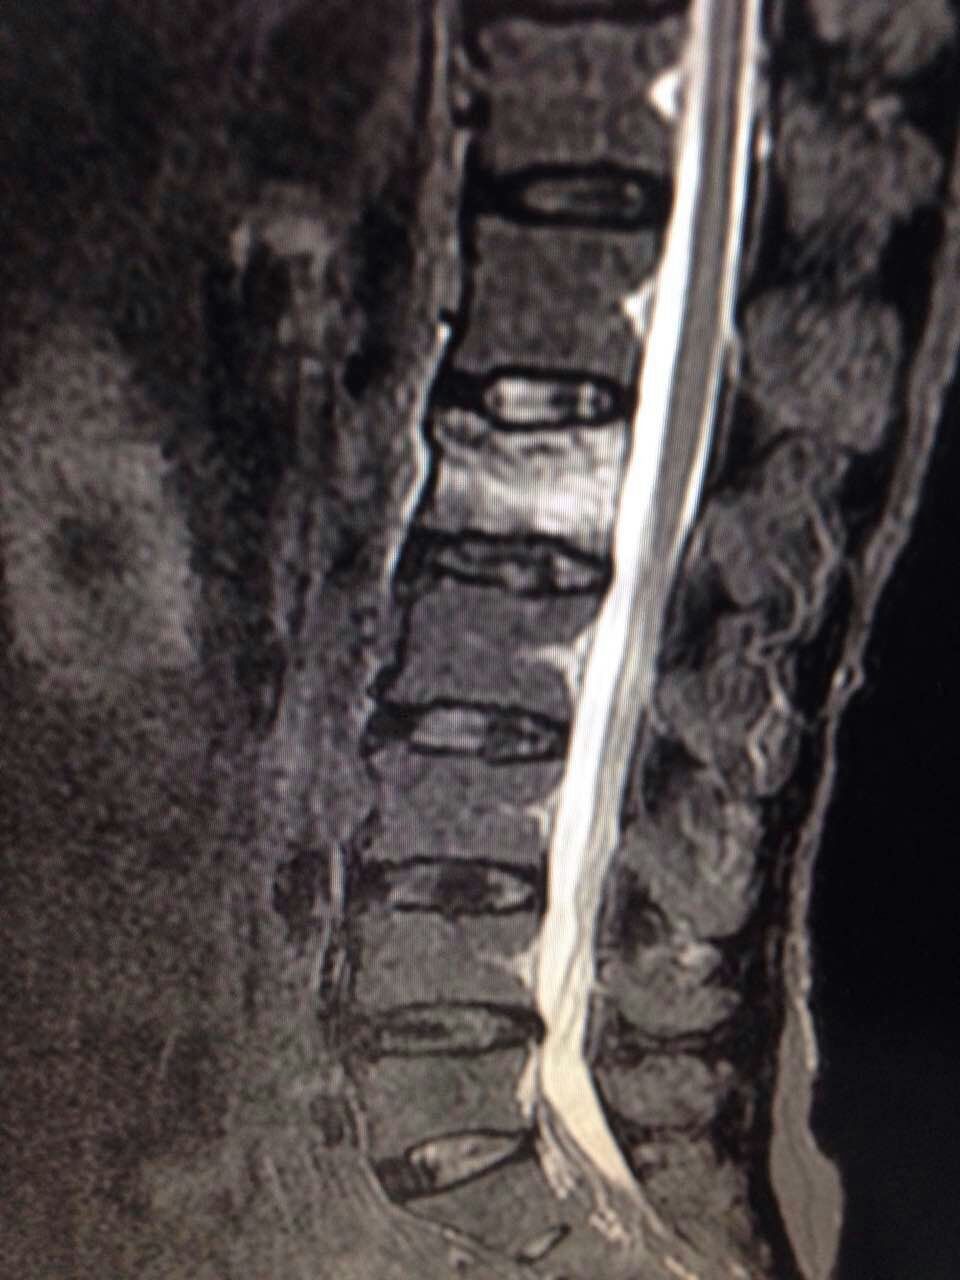

腰1椎体压缩性骨折,核磁示骨髓水肿